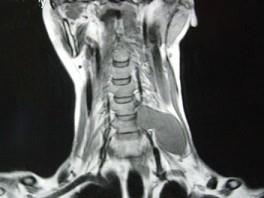

问题 52岁女性患者,左颈部无痛性包块渐进性增大,MRI检查如图,应考虑为 ( )

选项 A、左侧颈部转移癌 B、左侧颈部脂肪瘤 C、左侧颈部神经纤维瘤 D、左侧颈部动脉瘤 E、左侧颈部神经鞘瘤

答案 E